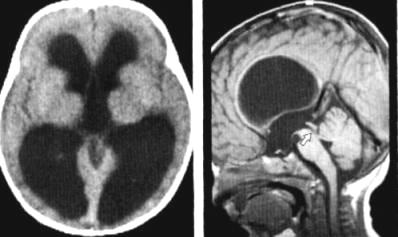

Комп'ютерна томографія (КТ) - у наш

час КТ займає домінуюче положення серед методів діагностики гідроцефалії. Це

технічно складний, але безпечний, надійний і безболісний спосіб діагностики

гідроцефалії. Пучок рентгенівських променів проходить крізь тіло пацієнта, а

зображення внутрішніх органів (у даному випадку мозку) створюються комп’ютером.

Саме дослідження займає від 5 до 10 хвилин. Ш,ь)

Магнітно-резонансна томографія (МРТ)

- цей метод діагностики також дозволяє одержати зображення мозку, але без

використання рентгенівських променів. В МРТ застосовуються радіохвилі і дуже

потужний магніт. За даними МРТ визначаються форма і ступінь важкості

гідроцефалії. Ці дослідження незамінні для уточнення причин виникнення водянки

мозку. МРТ - безболісна процедура, що не має побічних ефектів. Стандартне

дослідження проводиться в межах 30-40 хв. Щ,ь,ю)